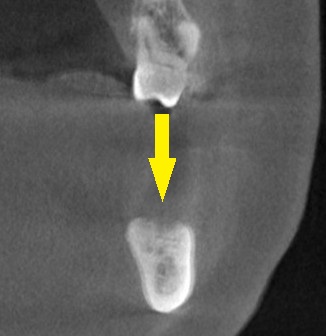

3か月ほどして、CTを撮影してみると、下の写真2段目のように、大きく骨欠損となっていました。

2本のインプラント埋入を目指したいのですが、2本目の部位では、下方に通っている神経までの距離は3~4mm程度でした。

ショートインプラントでも厳しいので、この場合は、人工骨を用いて、上方に骨を増やす手術を併用する計画としました。